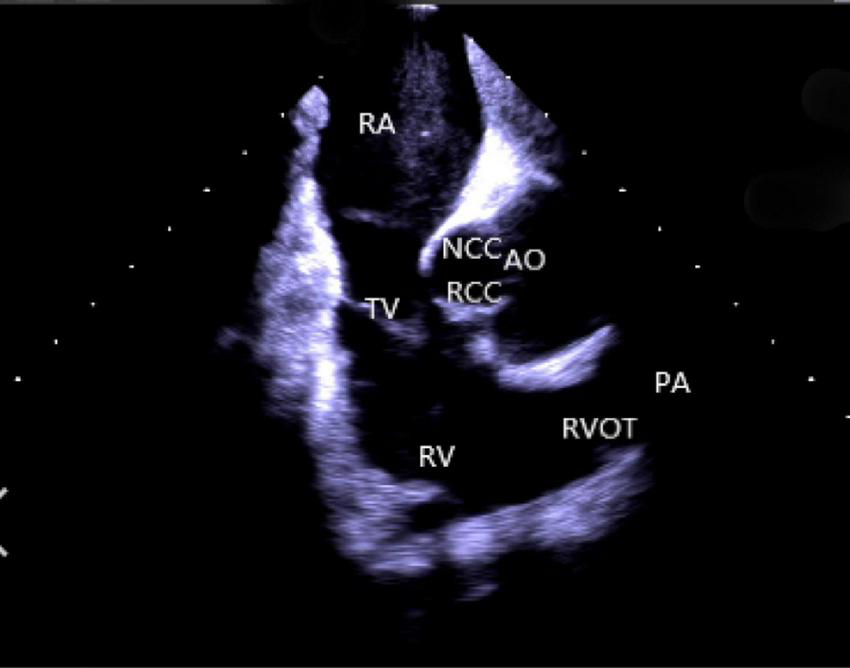

(2) Right atrium operation and view: After positioning the ICE catheter in the mid-right atrium (RA) through the inferior vena cava, the catheter was rotated so that the ultrasound probe points to the center of the tricuspid valve (TV), thereby reaching the HomeView position. This important position provided imaging of the RA, TV, right ventricle (RV), aortic long axis, non-coronary, and right coronary cusps, as well as a small part of the right ventricle outflow tract (RVOT) (Figure 1). From the HomeView position, a clockwise rotation exhibited the RV long axis model, showing the RA, coronary sinus, non-coronary and left coronary cusps, and part of the left ventricle (LV). Further clockwise rotation identified the left atrium (LA) and displayed the LA, RA, coronary sinus, left atrial appendage, mitral valve, and LV, respectively (Figure 2).

FIGURE 1

Homeview position. RA, right atrium; TV, tricuspid valve; RV, right ventricle; NCC, non-coronary cusp; RCC, right coronary cusp; AO, aortic valve; RVOT, right ventricular outflow tract; PA, pulmonary artery.